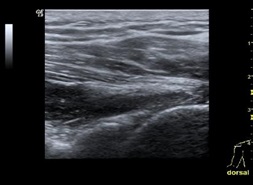

Alle bildene nedenfor er av høyre skulder. I tråd med konvensjon beskrevet ovenfor er markøren på proben rettet lateralt og kranialt for undersøkelse av anterolaterale region og medialt og kranialt for undersøkelse av posteriore regioner av skulderen.

Position 6: Infraspinatus, teres minor, posteriore recess og den spinoglenoidal notch

Hånden plasseres på låret med håndflaten opp. Proben dorsalt på skulderen i transversalplanet og lett vinklet langs infraspinatussenen mot caput humeri.

I denne posisjonen kan man visualisere den sentrale senen til infraspinatus i dens longitudinelle akse, labrum og glenoid.

Proben beveges medialt for å undersøke den spinoglenoidale notch.

Etter visualisering av den spinoglenoidale notch følger man infraspinatussenen mot festet på det midtre posteriore aspektet av tuberculum majus.

Ved å flytte proben inferiort visualieres teres minor senen. Denne ligger mer superficielt over muskelbuken sammenlignet med infraspinatussenen.

Proben plasseres transverselt over den muskelotendinøse overgangen mellom infraspinatus og teres minor og flyttes lateralt for å visualisere senene.

Armen innad- og utadroteres passivt under undersøkelsen av den spinoglenoidale notch, glenoid/labrum og infraspinatus-/teresminorsenene.